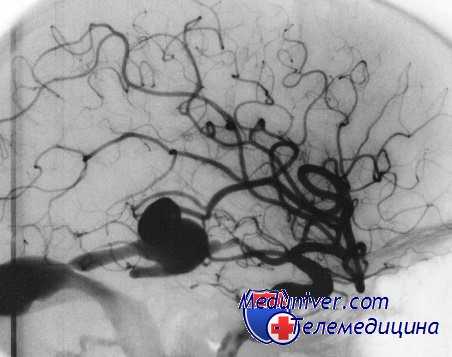

Интраоперационный разрыв аневризмы (ИОРА) возникает с частотой 5,6—35%. Интраоперационный разрыв аневризмы могут происходить на всех этапах операции, предшествующих выключению аневризмы из кровотока: во время вводного наркоза и интубации трахеи, краниотомии, вскрытия твердой мозговой оболочки, арахноидального доступа к аневризме, выделения несущей аневризму артерии и во время клипирования аневризмы.

По механизму возникновения выделяют внеконтактные и контактные интраоперационные разрывы аневризмы. Внеконтактными являются интраоперационные разрывы аневризмы, происходящие на ранних этапах операции, когда исключено механическое воздействие на купол аневризмы.

Внеконтактные интраоперационные разрывы аневризмы составляют 2,5—9% от общего количества интраоперационных разрывов аневризм. Внеконтактные интраоперационные разрывы аневризмы возникают при перекладывании больного на операционный стол, проведении вводного наркоза, интубации трахеи, при разрезе кожи, трепанации и вскрытии твердой мозговой оболочки, при выведении ЦСЖ по поясничному или вентрикулярному дренажу.

К. Houkin и соавт. также выделяют понятие ранних интраоперационных разрывов аневризмы, происходящих до полного выделения аневризмы и несущего аневризму сосуда, когда невозможно адекватно контролировать кровотечение.

Ключевым звеном патогенеза внеконтактного разрыва аневризмы в большинстве случаев является увеличение трансмурального давления на стенки аневризмы, обусловленное подъемом АД, либо снижением давления в субарахноидальном пространстве. Подъем АД может быть следствием прессорной реакции в ответ на болевую афферентацию при недостаточном обезболивании во время интубации трахеи, разрезе кожи и твердой мозговой оболочки.

Уменьшение давления в субарахноидальном пространстве возникает при аспирации сгустков крови и ЦСЖ из арахноидальных цистерн, выведении ЦСЖ через поясничный и вентрикулярный дренаж. Первый признак развития внеконтактного интраоперационного разрыва аневризмы — спонтанный, ничем, казалось бы, не вызванный подъем АД, который через 15-20 минут сменяется артериальной гипотензией (АГ).

Контактные интраоперационные разрывы аневризмы происходят в 91-94% наблюдений. Контактные интраоперационные разрывы аневризмы в большинстве случаев являются следствием механического воздействия на стенку аневризмы — ее растяжения и разрыва во время ретракции мозга шпателями, повреждения инструментами при тупой диссекции и разреза купола — при острой арахноидальной диссекции, раздавливания браншами клипса при клипировании аневризмы.

Следует отметить, что прорезывание шейки аневризмы клипсом в подавляющем большинстве случаев происходит либо при атеросклеротическом поражении пришеечной части аневризмы, либо при неполностью выделенной шейке многокамерной аневризмы. Контактные интраоперационные разрывы аневризмы также могут происходить при попытке коагуляции аневризмы и возникать в результате отделения тромба от места первоначального разрыва аневризмы во время арахноидальной диссекции и аспирации внутримозговой гематомы.

Для анализа интраоперационных осложнений нами была выделена группа из 301 больного, оперированных одним нейрохирургом. Интраоперационные разрывы аневризмы были зафиксированы у 47 (15,6%) больных. Контактные интраоперационные разрывы аневризмы произошли у 46 из 47 пациентов — в 98% наблюдений: во время начальной арахноидальной диссекции — в 7%, во время выделения несущей аневризму артерии — в 7%, при выделении и клипировании аневризмы — в 63 и 24% случаев соответственно.

По сводным данным других авторов, интраоперационные разрывы аневризмы возникают наиболее часто при арахноидальной диссекции — в 48—81% и реже — при клипировании аневризмы — в 18—45%, при аспирации внутримозговой гематомы — в 3% и при манипуляциях шпателями — в 3% случаев.